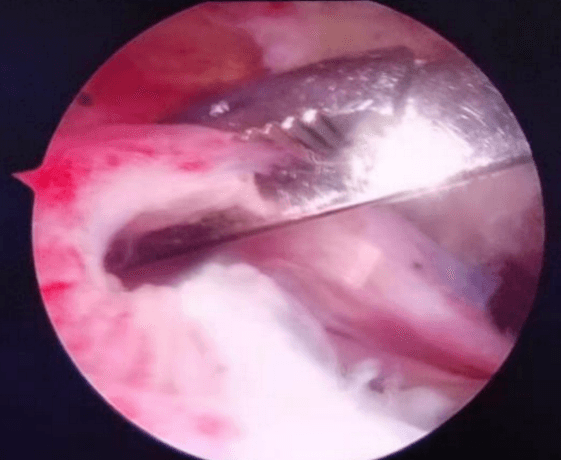

肩袖損傷手術

擅長治療各種骨關節外傷、骨關節疾病。手術方面擅長髖、膝關節置換術、膝關節單髁置換術、脛骨高位截骨術、股骨頸骨折及轉子間骨折等手術。富血小板血漿(PRP)治療骨關節炎。擅長關節鏡下膝關節交叉韌帶重建、半月板損傷縫合、髕骨脫位、肩袖修補,肩峰撞擊征、鈣化性肌腱炎,肱二頭肌長頭腱炎,髖關節盂唇損傷、髖關節撞擊征、踝關節不穩、踝關節韌帶損傷、肩關節不穩、肩周炎、各類關節內骨折、關節脫位的手術治療。

七年前從零出發,從無到有,從有到精,李鵬主任帶領團隊人員,先后在西安、上海、北京、廣州等獨家頂級關節運動醫學中心學習,屢次開創引進新技術,填補我院多項技術空白。先后開展了首例膝關節鏡、首例肩關節鏡手術,首例踝關節鏡手術,首例肘關節鏡手術,首例髖關節鏡手術,完成了技術要求高、難度大的肩袖損傷修復手術、肩關節復發性脫位、BanKart損傷修復手術,后交叉韌帶下止點骨折、膝關節多發韌帶損傷重建手術等,標志著我院在骨關節運動醫學專業及關節鏡微創手術技術的顯著提升。